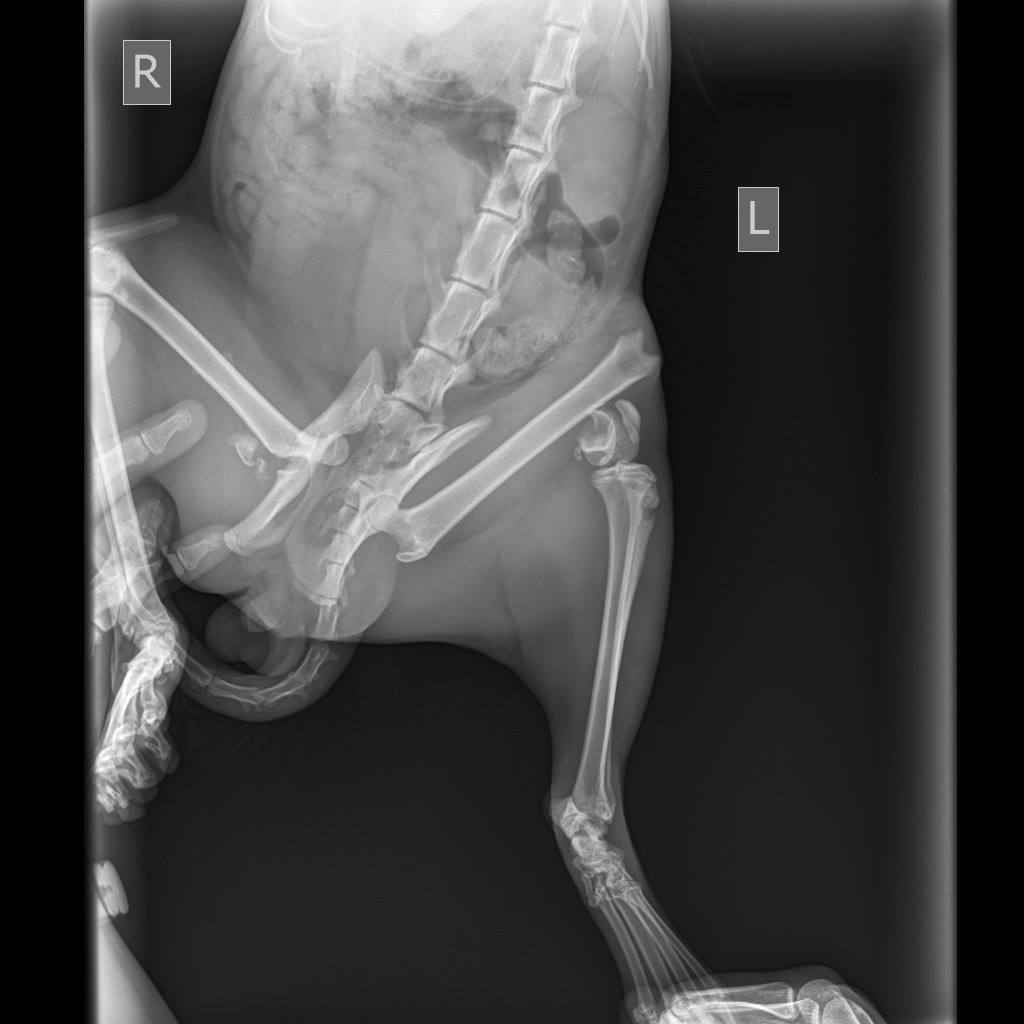

В прошлое воскресенье, молодые люди нашли котика с перебитыми задними лапами. Не смогли пройти мимо, и оставить красавца на верную смерть. Повезли в клинику. Анализы, обследования, осмотры. У котейки не нашли инфекций, но с лапками беда. Сложные переломы, и единственный выход, это остеосинтез. Начали поиск клиник и хирургов которые проведут операцию. Цены озвучивались от 40 до 100 тысяч за одну лапку(. Но ребята не сдавались, и продолжали поиски. Параллельно обратились в различные фонды, но во всех получили отказ.

И всё же, молодые люди смогли найти хирурга, который согласился прооперировать котана за 50 т. обе лапы. Плюс ОРИТ минимум на неделю. А это ещё 10 т. в сутки.

Вчера была проведена операция. Всё прошло не плохо. Коту дополнительно поставили стому, что бы докармливать. Но после операции начал падать гематокрит и эритроциты. Нужно переливание крови.